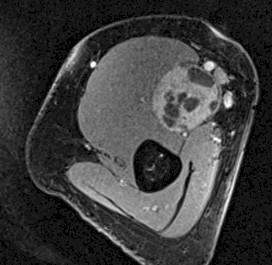

Como exploraciones complementarias se realizó una ecografía y una resonancia magnética (RM) que describió un tumor sólido en la continuidad del nervio mediano, de baja densidad y sin realce vascular (figuras 1a y 1b).

Figuras 1a y 1b: Imágenes de la resonancia magnética (RM) en las que observamos un corte en el plano parasagital y en el plano transversal de la tumoración a nivel del brazo.